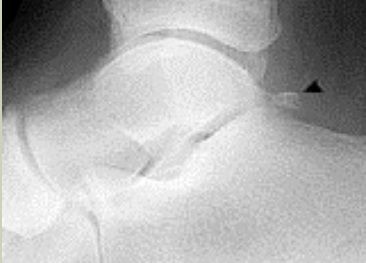

What disease is this? What does the arrow indicate? | Rheumatoid arthritis. Arrow = Bone erosion secondary to inflammation of retrocalcaneal bursa. |